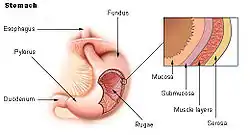

The gastrointestinal wall of the gastrointestinal tract is made up of four layers of specialised tissue. From the inner cavity of the gut (the lumen) outwards, these are:

The mucosa is the innermost layer of the gastrointestinal tract. It surrounds the lumen of the tract and comes into direct contact with digested food (chyme). The mucosa itself is made up of three layers:[1] the epithelium, where most digestive, absorptive and secretory processes occur; the lamina propria, a layer of connective tissue, and the muscularis mucosae, a thin layer of smooth muscle.

The submucosa contains nerves including the submucous plexus (also called Meissner's plexus), blood vessels and elastic fibres with collagen, that stretches with increased capacity but maintains the shape of the intestine.

The muscular layer surrounds the submucosa. It comprises layers of smooth muscle in longitudinal and circular orientation that also helps with continued bowel movements (peristalsis) and the movement of digested material out of and along the gut. In between the two layers of muscle lies the myenteric plexus (also called Auerbach's plexus).

The serosa/adventitia are the final layers. These are made up of loose connective tissue and coated in mucus so as to prevent any friction damage from the intestine rubbing against other tissue. The serosa is present if the tissue is within the peritoneum, and the adventitia if the tissue is retroperitoneal.

General organisation of GI tract The wall of the stomach.